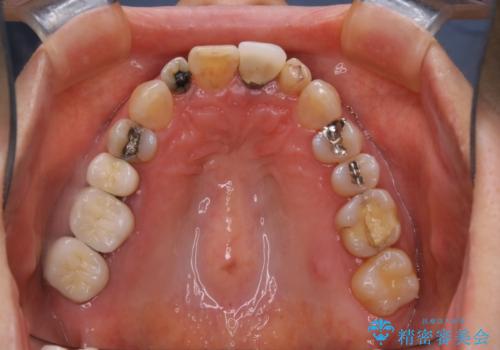

大きな詰め物を被せ物に変えて、歯の破折リスクを減らす

- 以前に異なる種類の材料で継ぎ接ぎ状態で修復されており、隙間のところから虫歯が再発していました。歯の手前側と後方及び内側に亀裂も入っていたため、将来的な虫歯再発のリスク及び歯の破折リスクを最小限にとどめるよう、被せものにて治療を行いました。

適合不良の補綴物は二次的な虫歯発生のリスクが高まります。

自費診療で用いられる材料は保険適応の材料に比べて、より精密で適合の良い被せ物作ることができるため、長期的な虫歯のリスクを大幅に減らすことが可能です。